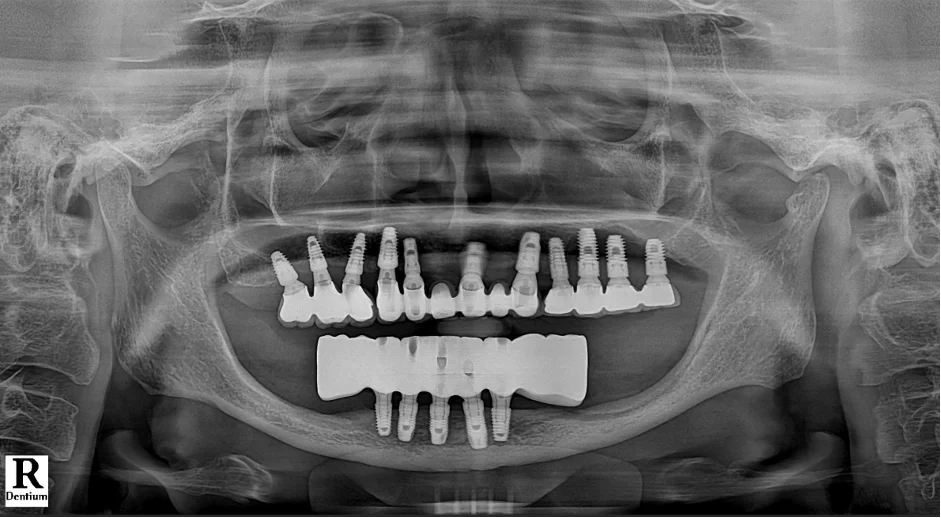

모든 치료가 끝난 후 방사선 사진을 확인해 보면,

총 5개의 임플란트가 전체 보철물을

안정적으로 지지하고 있는 것을 볼 수 있습니다.

[📸 치료 후 엑스레이] (촬영일: 2025년 3월)